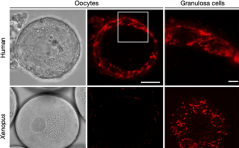

Präferenz der Transmänner für gynäkologische Untersuchungen / Wie überleben Eizellen über Jahrzehnte ohne Schaden? / Folsäureprävention: richtig verstanden und umgesetzt? / Sectio-Nischenresektion und Myo-metriumdicke / Sonographische Beurteilung des ... PDF DokumentWussten Sie schon